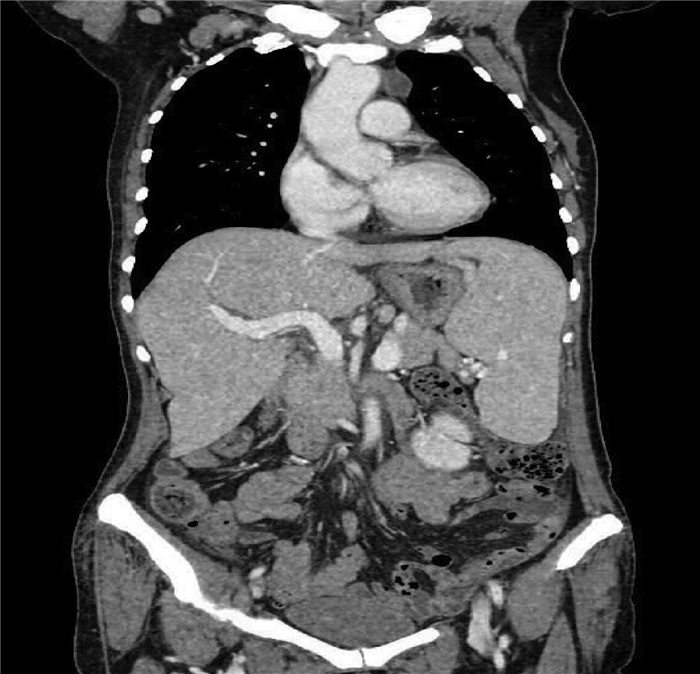

A preliminary study on percutaneous transhepatic drainage combined with sequential percutaneous nephroscopy in treatment of refractory liver abscess

Changhu DUAN, Xiaochen LIU, Jianlong DING, Jianfeng DUAN, Xirong ZHAO, Fan YANG, Ling WU, Lifei ZHAO, Sheng TAI

2021, 37(11): 2622-2625. DOI: 10.3969/j.issn.1001-5256.2021.11.026

Abstract(1082) HTML (221) PDF (2925KB)(64)

Abstract:

Objective  To investigate the clinical effect of percutaneous transhepatic drainage combined with sequential percutaneous nephroscopy for necrosectomy and drainage in the treatment of refractory liver abscess after transcatheter arterial embolization (TACE).  Methods  A retrospective analysis was performed for three patients with refractory liver abscess after TACE in The Affiliated 3201 Hospital of Xi'an Jiaotong University School of Medicine from January 2018 to December 2020, and among the three patients, one had the formation of liver abscess after TACE for hepatic metastases after pancreaticoduodenectomy, one had liver abscess after repeated TACE for massive hepatocellular carcinoma, and one had secondary liver abscess after TACE for traumatic hepatic rupture. All three patients received percutaneous transhepatic drainage and sequential percutaneous nephroscopy for the treatment of refractory liver abscess, and their specific treatment process was summarized.  Results  All three patients were diagnosed with refractory liver abscess based on CT, routine blood test, procalcitonin, blood culture, and clinical manifestation. Percutaneous transhepatic catheterization under the guidance of conventional ultrasonography or CT and effective antibiotics had an unsatisfactory therapeutic effect, and after sequential percutaneous nephroscopy was performed for necrosectomy and drainage, liver abscess was cured and the patients had good prognosis.  Conclusion  For refractory liver abscess after TACE, when routine puncture treatment has an unsatisfactory therapeutic effect or a patient cannot tolerate surgical operation, percutaneous transhepatic drainage combined with sequential percutaneous nephroscopy is safe and effective in the treatment of refractory liver abscess.